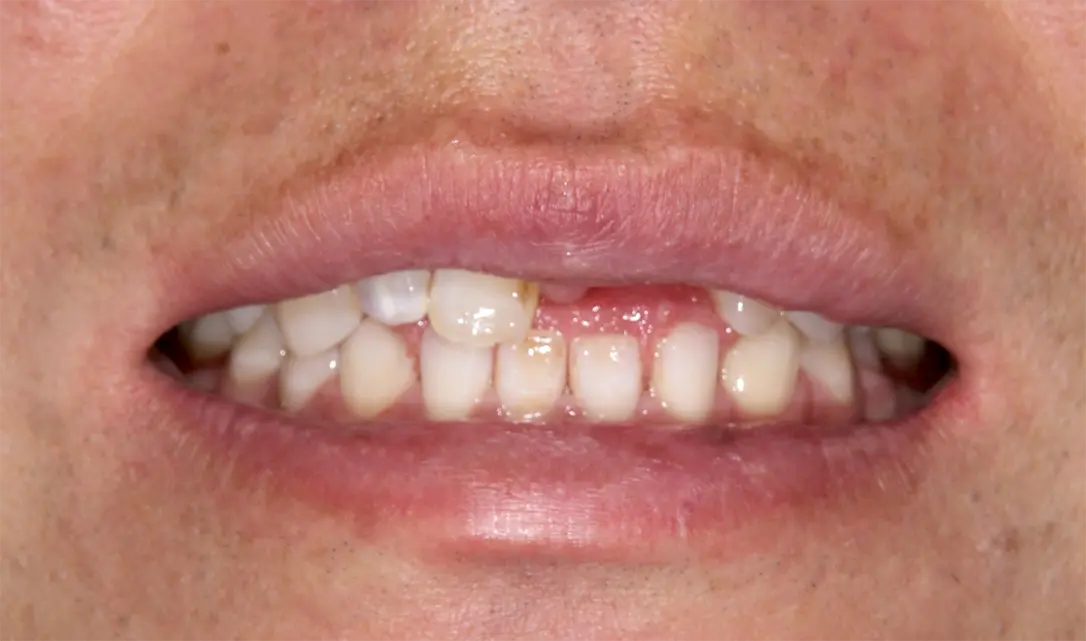

症例1

初診時

| 治療名称 | 右上2先天性欠損のため矯正治療を行ない、同部インプラント治療による審美的な改善。 |

| 患者の症状 | 生まれつき側切歯(2番目の歯)がなく、犬歯がずれた位置にあり、前歯がそろっていないので見た目をきれいにしてほしい。 |

| 治療方法 | 矯正治療により左右のバランスを整えるため、側切歯(2番目の歯)にスペースを確保し、同部にインプラントを埋入しセラミックで審美修復する。 |

| 治療結果 | 術後10年以上経過しているが、審美的にも機能的にも改善された状態にご自身でも非常に満足されている。 |